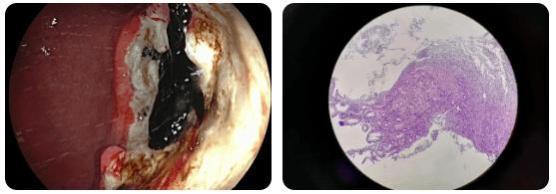

病例1:35岁,查出进展期胃癌:今年35岁的赵先生出现胃胀、嗳气的症状已经一年多了,但因为一直在外地工作,怕麻烦,也不能报销,就自己在药店买药吃。直到半年前,开始频繁胃痛,药房的人给推荐他了几种胃药,吃了几个月,还是不见好,他这想才到医院做个胃镜检查。

通过胃镜检查,发现一个巨大的溃疡性病灶!医生取了活检,几天后病理报告出来了,赫然写着: (胃窦、胃角)考虑恶性肿瘤;建议免疫组化检查除外低分化癌及淋巴瘤。